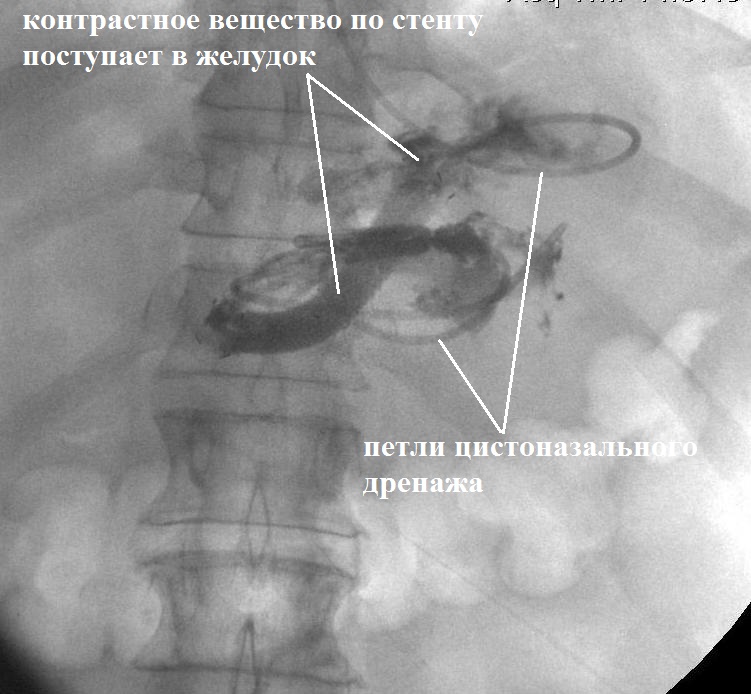

Принято решение о выполнении редренирования ОЖС с установкой дренажа большего диаметра. 06.10.2017 г. выполнена эндоскопическая установка цистогастрального саморасширяющегося стента-эндопротеза для псевдокист диаметром 12 мм (рис. 5 А, Б).

Рис. 5. Редренирование сальниковой сумки и контрольное рентгенконтрастное исследование (71-е сут болезни). А — схема редренирования сальниковой сумки с установкой стента

Рис. 5. Редренирование сальниковой сумки и контрольное рентгенконтрастное исследование (71-е сут болезни). Б — интраоперационная рентгенограмма

В послеоперационном периоде проводилось ежедневное промывание полости сальниковой сумки 0,05%-ным раствором хлоргекседина биглюконата через цистоназальный дренаж. На фоне проводимого лечения отмечена нормализация температуры тела и лабораторных показателей. При рентгенофистулографии от 12.10.2017 г. выявлены значительное уменьшение размеров ОЖС сальниковой сумки, свободное поступление рентгеноконтрастного препарата в просвет желудка (рис. 5 В).

Рис. 5. Редренирование сальниковой сумки и контрольное рентгенконтрастное исследование (71-е сут болезни). В — контрольная фистулография на 6-е сут после повторного дренирования ОЖС сальниковой сумки